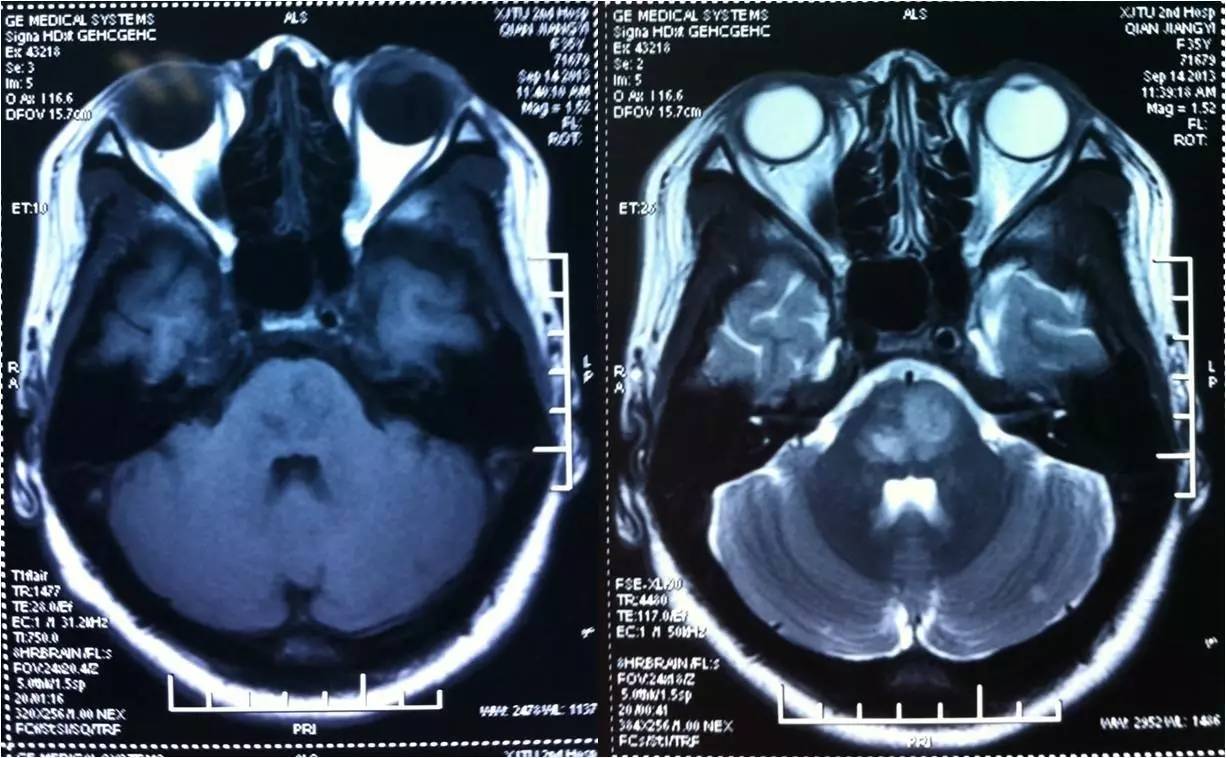

》某女,35岁,言语不清,右侧肢体无力12h ;

》急性发病,渐加重,伴一过性耳鸣、头晕 ;

》4天前解剖宫产手术;

》查体:T37.4℃,BP101/60mmHg,言语不能,双侧面瘫,张口不能,吞咽障碍,左上肢肌力3级,下肢1级,右侧上下肢肌力0级,上肢肌张力减低,下肢增高,双侧病理征阳性,脑膜刺激征阴性;

》头颅CT未见异常。

3

术后情况

》呼吸平稳,口腔分泌物减少,吞咽功能改善。

》能简单回答问题,左侧肢体肌力4级。

>>术后1天

>>预后

出院情况:

右侧中枢性面、舌瘫,右上肢肌力1级,下肢3级,左侧肌力4级,右侧偏身痛觉减退,右侧病理征阳性。

60天及90天预后:

mRS评分1分; mRS评分0分。